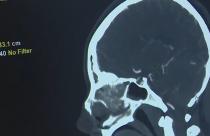

Общество Саратовские врачи спасли 20-летнюю девушку с инсультом янв 29, 2026 В областной клинической больнице успешно провели операцию с острым нарушением мозгового кровообращения